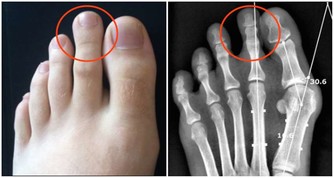

這時,病菌乘虛而入襲擊機體,容易引發各種呼吸系統疾病,導致感冒、氣管炎、關節炎等疾病。

因此,“春捂”應重點做好手腕、腰部、肚臍、小腿及雙腳保暖。

厚褲和厚襪不可過早減去,並常用熱水泡腳,睡覺時下半身蓋厚一點。